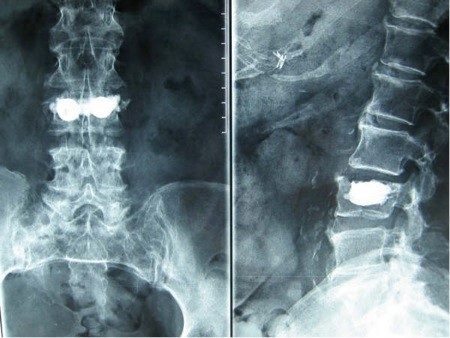

Corpul vertebral este prezentat la imaginile radiografice printr-un aspect alveolar sau de „fagure de albini”, cu respectarea integrității corticalei osoase și a discului intervertebral.

Hemangioamele mici pot fi urmărite în dinamică timp îndelungat. Pentru hemagioamele mari, există două oportunități terapeutice: radioterapie și chirurgie. Metoda de radioterapie ține de trecut, când nu era posibil tratamentul chirurgical. Acum tratamentul chirurgical constă în practicarea unui procedeu minim-invaziv, numit cimentoplastie vertebrală percutană. Decizia finală este luată în baza semnelor neurologice prezente, dar și a preferințelor pacienților. Cimentoplastia vertebrală constă în injectarea percutană (fără de incizii) în corpul vertebral a unui ciment special, cu scop de prevenire a fracturilor patologice. Scopul cimentoplastiei este de a îmbunătăți rezistența vertebrei prin umplerea acesteia cu ciment și prevenirea fracturii patologice. Pacientul poate fi ridicat în picioare la patru ore de la operație și poate mearge acasă a doua zi, revenind la activitățile sale anterioare într-o săptămână.